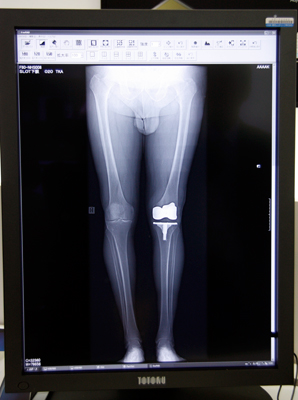

ブースの一角にはアプリケーションギャラリーが設けられ,最新のFPDアプリケーションが紹介された。スロットラジオグラフィは,幅の狭いX線ビームを被検者に対して直角に照射することで,歪みのない長尺画像を得ることができる。頸椎から骨盤,腰から足先と,始点と終点を指定するだけの簡単操作で,短時間で自動撮影・再構成を行う。精度の高い画像が得られることで,整形外科領域においては距離計測の精度が高まり,正確な手術計画が可能となる。

safireシリーズのFPDが持つ,高いコントラスト分解能を有効利用するアプリケーションの1つであるトモシンセシスは,より改良を重ねた新しい画像再構成処理を開発中で,高性能型トモシンセシスとして今夏のリリースを予定している。逐次近似法と,島津独自の金属アーチファクトを除去するアルゴリズムを組み合わせることで,金属を埋め込んでいる整形領域の撮影でも,金属と骨の境界が明瞭な,アーチファクトの少ないクリアな画像を得られるようになっている。また,被ばく低減についても,新画像再構成処理を施すことで撮影枚数を減らしても同等の画質を得ることができ,被ばく線量を抑えることが期待できるという。トモシンセシスは,従来の標準タイプと,この新再構成処理法の高性能タイプを提供していく予定で,標準タイプからのアップグレードにも対応する。

![]() スロットラジオグラフィで撮影した 人工骨の埋設手術後の確認画像 |